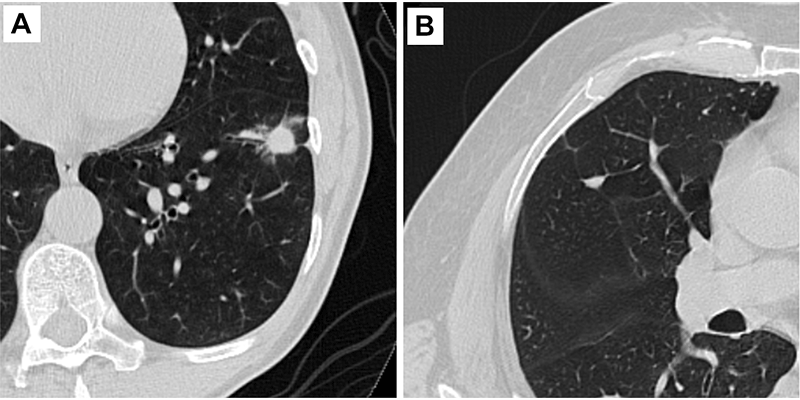

Representative axial CT images of pulmonary nodules included in the study. (A) Malignant nodule with a lung cancer prediction score of 10. (B) Benign nodule with a lung cancer prediction score of 2.

Kim et al, Radiology 2022; 000:1-9 © RSNA 2022